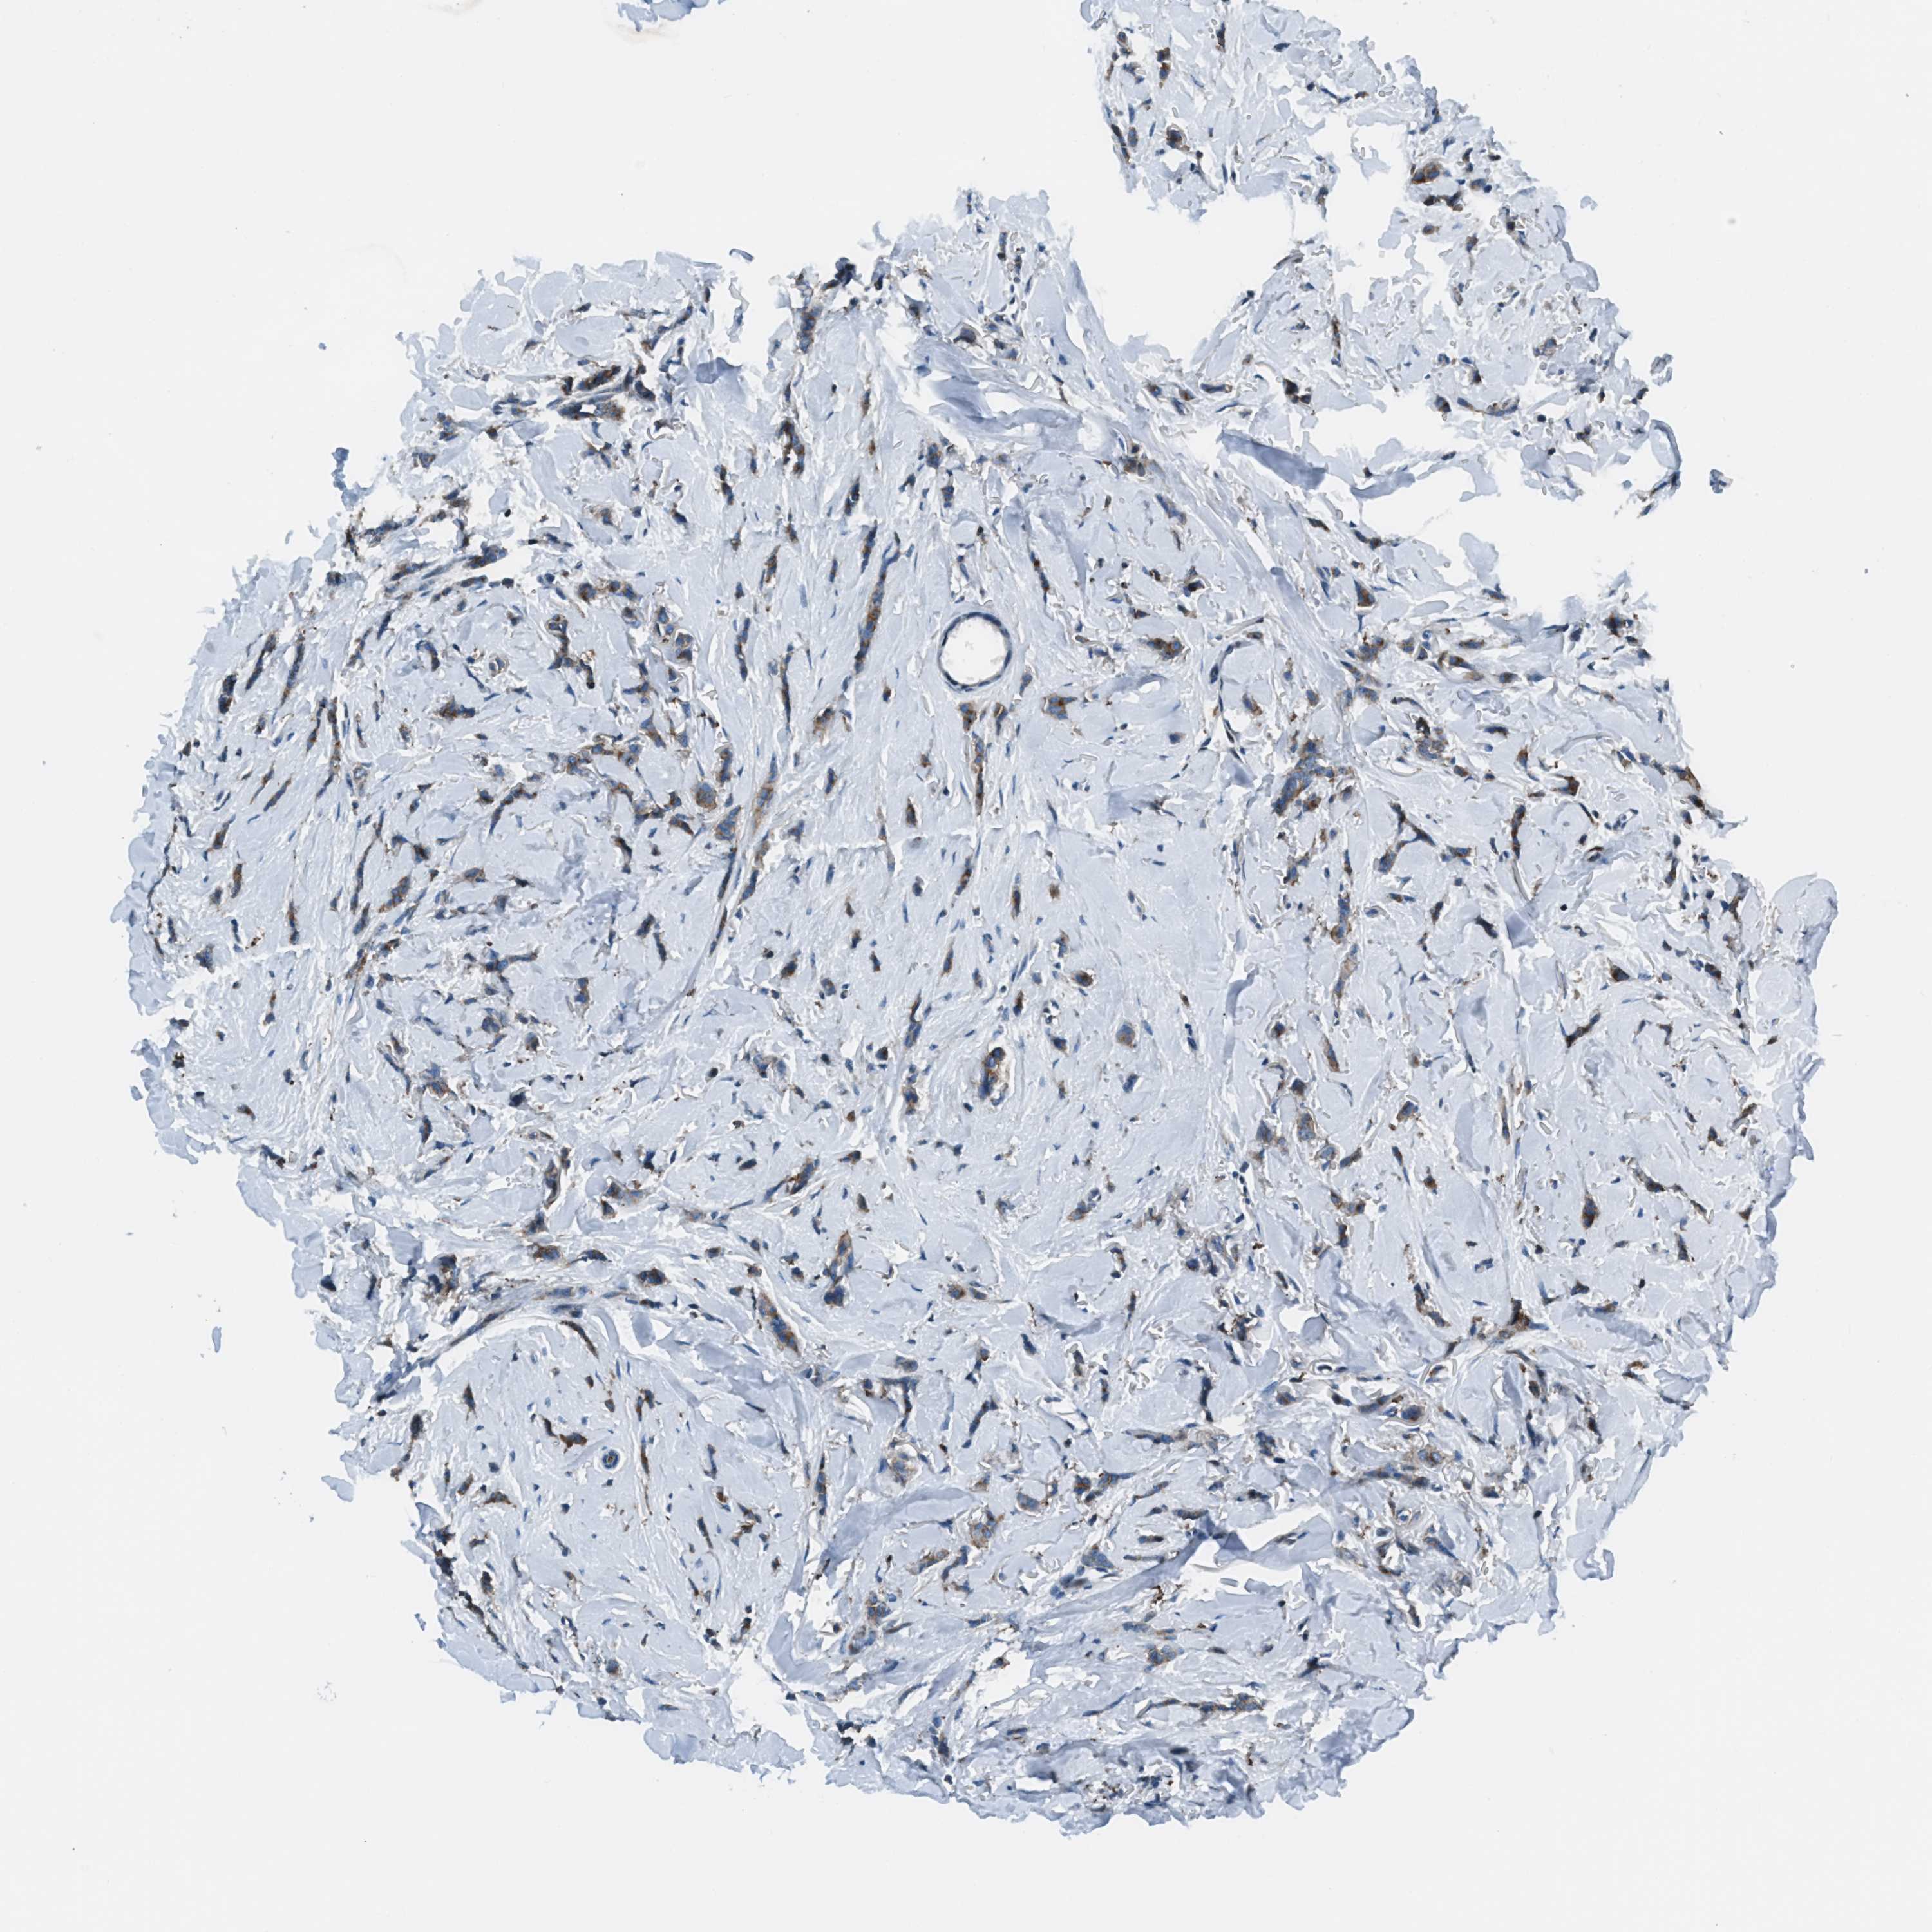

BRCA TCGA BRCA VALIDATION PROTEIN EXPRESSION